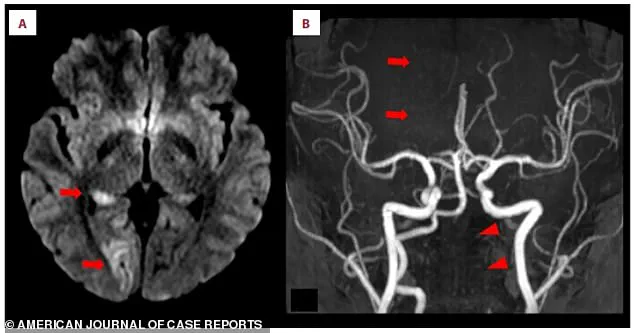

MRI scans painted a clear picture of the crisis.

Panel A revealed bright white spots in the right occipital lobe, a region critical for vision.

These bright signals, called hyperintensities, indicated a lack of blood flow due to the stroke.

Panel B showed a missing section of the right posterior cerebral artery, a key blood vessel, confirming the blockage.

Lower arrows on the same scan pointed to the left vertebral artery in her neck, which appeared faint or broken. “This artery is like the lifeline to the brain,” explained Dr.

Martinez. “When it’s compromised, the brain is starved of oxygen, and that’s when the damage begins.”